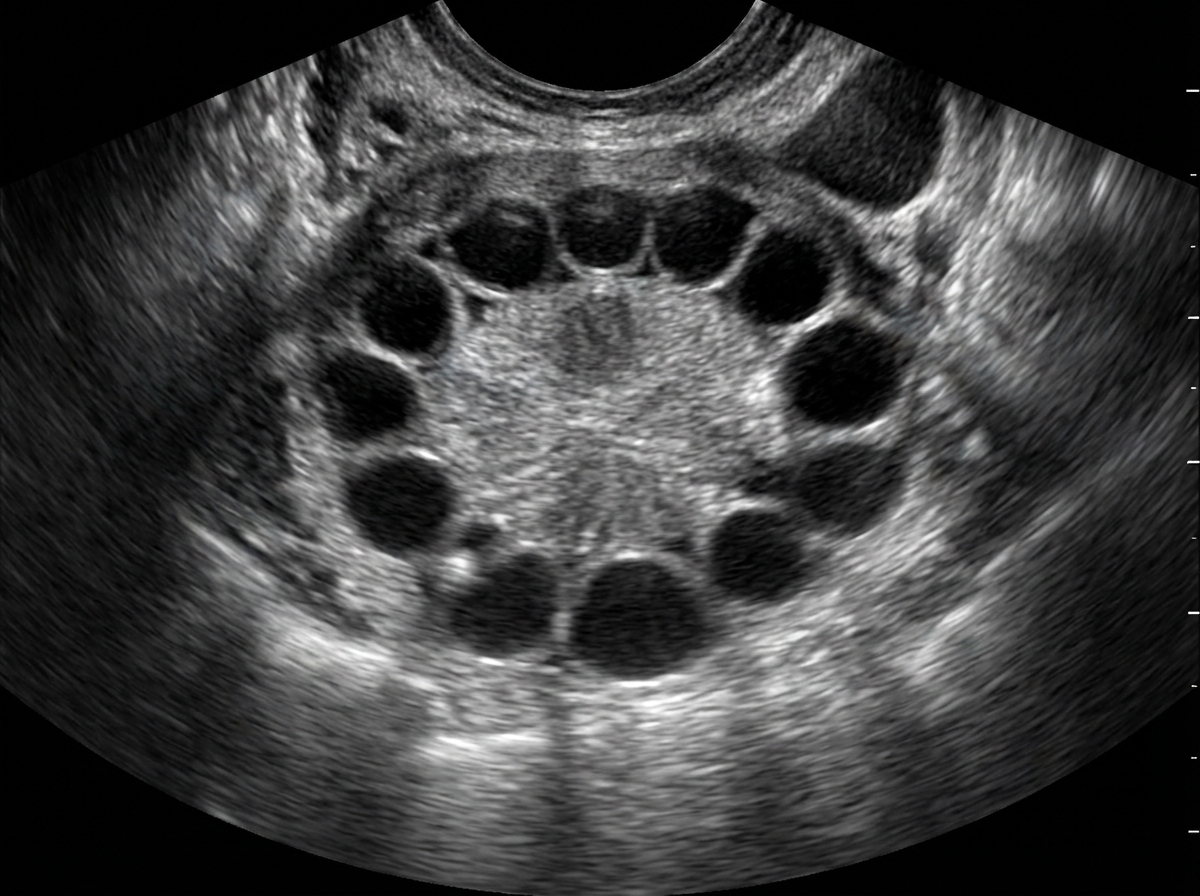

Intrauterine Devices

Practice Questions